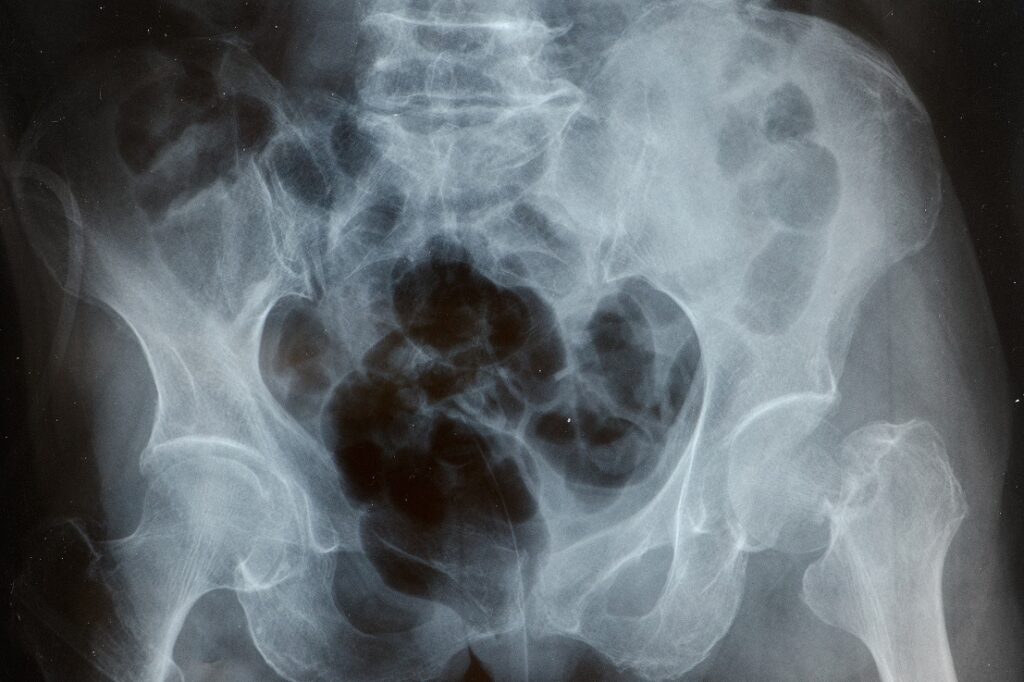

La histerosalpingografía (también conocida como HSG) es un estudio con rayos X y medio de contraste que ayuda a ver el interior del útero y comprobar si las trompas están permeables. No es un examen para “adivinar”: es para tener información concreta y tomar decisiones con tu ginecólogo sobre fertilidad, infertilidad y próximos pasos.

La histerosalpingografía es un procedimiento de imagen que utiliza rayos X y un medio de contraste para observar:

La forma y el contorno interno del útero (cavidad uterina).

El paso del contraste a través de las trompas de Falopio, verificando si están permeables u obstruidas.

La histerosalpingografía (HSG) destaca cuando el objetivo es ver, con imágenes, el trayecto del contraste y la cavidad uterina. No reemplaza todo, pero sí puede ser una pieza clave de diagnóstico para orientar el plan.

El objetivo del estudio es aportar un diagnóstico claro sobre la cavidad del útero y la permeabilidad de las trompas de Falopio. Tu ginecólogo usará esa información para orientar el siguiente paso en tu plan de fertilidad.

La histerosalpingografía no define tu historia por sí sola, pero sí puede darte lo que hoy hace falta: claridad. Ver cómo está tu útero, cómo están tus trompas de Falopio, y llevarle a tu ginecólogo en Panamá información concreta para decidir el siguiente paso con criterio.